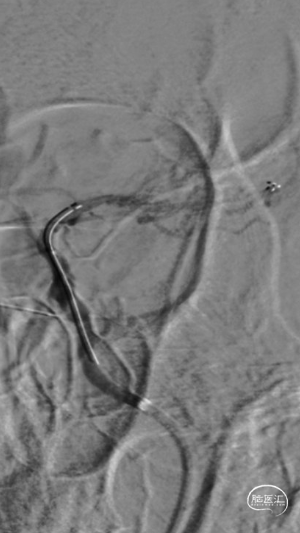

微导管越过大脑中动脉血栓后,以4-20mm Solitaire AB支架,配合6F 115cm SKATHI远端通路导管取栓一次,复查造影大脑中动脉血栓通畅,远端仍有少许血栓,观察后血流能够维持。

回撤SKATHI远端通路导管至C3段,通过导管再次释放SPIDER保护伞,回撤导管至颈总动脉,造影见C1段严重狭窄,以4-30mm球囊扩张狭窄段,复查造影狭窄段好转,远端再次闭塞,考虑斑块或血栓脱落,立即置入7-40 wallstent支架。

复查造影远端仍然闭塞,负压状态上行SKATHI远端通路导管回收保护伞并抽吸血栓,可见保护伞及大量血栓取出,复查造影C3段仍有血栓。再次上行SKATHI远端通路导管抽吸取栓,复查造影示远端血流通畅。